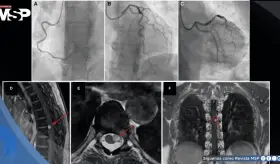

Tras múltiples evaluaciones cardíacas normales, estudios de imagen revelaron un schwannoma espinal a nivel D6-D7 como causa del dolor torácico neuropático.